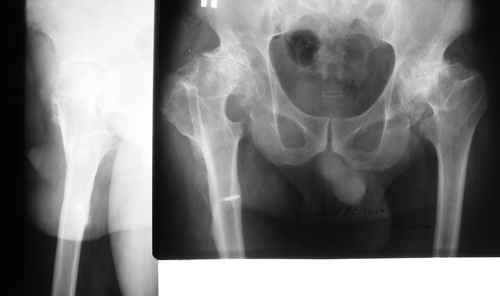

Эндопротезирование на фоне деформации после остеотомии бедра

пациент 60 лет.В 1980 году медиализирующая остеотомия правого бедра с фиксацией пластиной Петуховой.

В 2006 году произведено удаление пластины.В настоящий момент планируется эндопротезирование правого тазобедренного сустава.

В наличии эндопротезы De-Puy Corail, AML; Biomet, ножка Taperloc.

Возможные варианты установки ножки:

1)установить ножку в оси диафиза

2)установить ножку в вальгусном положении

3)выполнить поперечную остеотомию бедра на уровне смещения с последующим остеосинтезом ножкой эндопротеза.